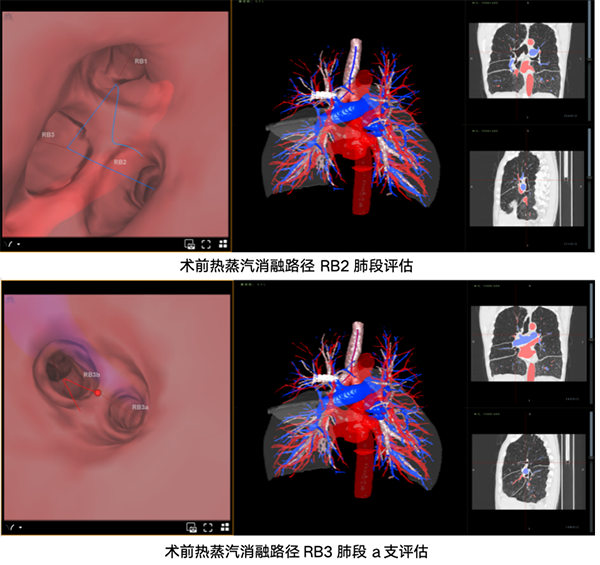

由于患者属于典型的非均质上肺肺气肿,双肺上叶多个肺段均需干预。术前,呼吸与危重症医学科(二)团队结合胸部CT与虚拟导航技术,对目标亚段支气管进行了细致的可及性及热剂量评估,精准规划出最优手术路径。

考虑到治疗范围较大,若同期处理双侧,患者的肺功能可能无法耐受。团队经过严密讨论,决定采取“分步走”策略:先行右肺热蒸汽减容,待三个月后右肺气道重构恢复,再择期进行左肺手术。

术中,赵焕主任通过支气管镜将热蒸汽导管精准置入目标肺段,利用导管末端球囊临时封闭靶段支气管后,将预先经影像软件精准定量的加热水蒸汽输送至病变区域。这些高温蒸汽会引发目标肺段可控的炎症修复反应,促使病变的细支气管和肺泡发生不可逆的纤维化与瘢痕形成。随着无功能的气肿肺组织逐渐萎缩、体积减小,便能为相对正常的肺组织“腾出”空间,有效改善肺部通气效率,缓解患者的呼吸困难症状。